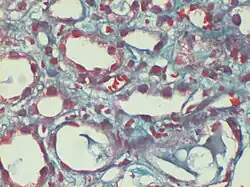

Gömöri trichrome stain

Gömöri trichrome stain is a histological stain used on muscle tissue.[2][3]

It can be used to test for certain forms of mitochondrial myopathy.